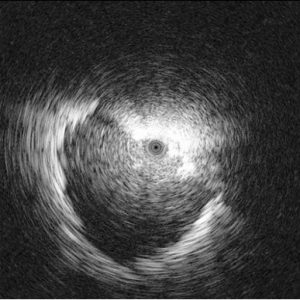

Για πρώτη φορά στη Βόρεια Ελλάδα ήρθε και εφαρμόζεται ο ενδοβρογχικός υπέρηχος RADIAL–ENDOBRONCHIΑL ULTRASOUND.

Είναι η τελευταία λέξη της τεχνολογίας για τη βιοψία μονήρη όζου (βλάβη κάτω από 3 cm) ή μάζας στην περιφέρεια του πνεύμονα (κάτω από 3cm). Γίνεται με μέθη, όπως η γαστροσκόπηση, διαρκεί το μέγιστο 20 λεπτά και διενεργείται ταυτόχρονα και ταχεία βιοψία, οπότε εξασφαλίζεται άμεσο αποτέλεσμα.

Εικόνες από τη διαδίκασια της ταχείας βιοψίας μέσα στην αίθουσα ενδοσκόπησης